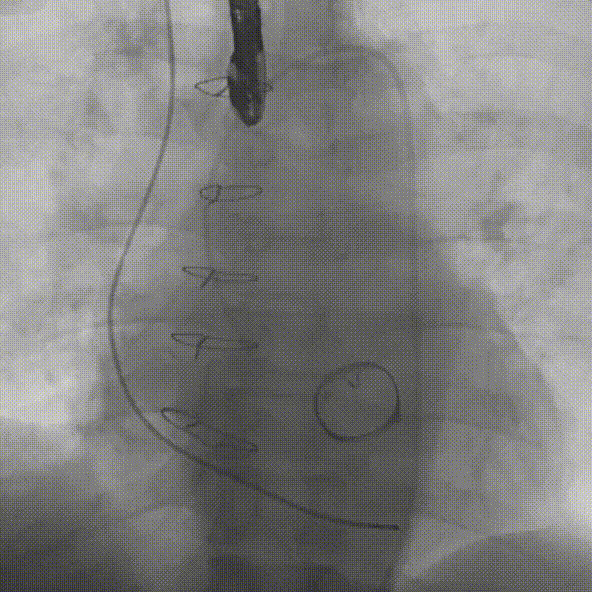

对于这样挑战的复杂病变,使用VenusA-Plus®可回收输送系统,为手术增加了一重保障,拟选择L29型号瓣膜经由右侧股动脉入路,选择标准位偏高2mm左右进行释放完成手术。瓣膜释放过程中,观察瓣膜位置,当瓣膜植入位置不合适,可以及时回收,重新调整位置再次释放,降低手术风险,提高手术成功率。

手术过程

在放射科,超声科和麻醉科的通力协作下,顺利完成了术前准备,术者团队在术中谨慎建立轨道,根据主动脉根部造影的结果,初步判断释放体位是否合适观察瓣叶活动度、是否合并反流,选择合适的跨瓣体位。瓣膜释放前优先确认猪尾管位置,避免瓣膜在释放过程中脱载。